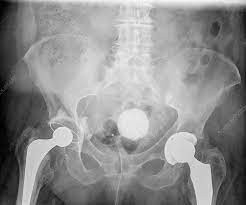

Reproductive Organ Calcification as a Cause of Infertility

Calcifications of the reproductive organs can go unnoticed and undiagnosed for years, and many patients with fertility issues never even suspect this as a potential cause for infertility. There isn’t much discussion about reproductive organ calcifications on the internet, unfortunately, but this doesn’t mean that it isn’t a problem. As more and more people stick to a traditional western diet, a range of nutritional deficiencies are becoming more likely. And, these nutrient deficiencies not only are proven to lead to organ calcifications, but also to other health problems.

Ovarian calcifications can negatively affect female fertility in that they can interfere with follicular development, oocyte release, and the synthesis of reproductive hormones. As we talked about in the article about Lunaception, the ovaries, like the hypothalamus (which is intimately connected with the pineal gland), also have circadian oscillators. So, similarly to pineal gland calcifications, ovarian calcifications may interfere with general reproductive rhythms, including ovulation and the timing of menstruation.Calcifications of the ovaries aren’t all that uncommon. Three different studies done in 1996, 2002, and 2007 indicate that, though some ovarian calcifications aren’t associated with any other health complications, that some can lead to the development of ovarian cysts of tumors. Women with PCOS may find this fact particularly interesting, since it suggests that underlying calcifications may actually be to blame in some cases for the development of numerous and/or painful ovarian cysts. Other conditions that ovarian calcifications have been associated with include:

Uterine Calcification / Endometrial Calcification

Calcifications in and around the uterus are another potential cause of infertility for some women. Uterine and endometrial calcifications have been associated with:- Recurrent miscarriage

Some studies have shown that surgical removal of uterine calcifications can increase the chances of pregnancy success by up to 55% or more. However, despite the fact that surgical removal of calcifications is sometimes possible, vitamin K2 supplementation, in combination with other supportive therapies, offers a non-invasive and truly healing method for getting rid of calcifications in the reproductive organs. What these studies do tell us, though, is that removal or dissolution of calcifications in the uterus by any means is likely to improve a woman’s fertility and chances of conceiving and carrying a healthy baby to term.

Fallopian Tube Calcification

Calcification of the fallopian tubes can lead to difficulties with fertilization of oocytes and eventual implantation of any eggs that may be fertilized. Blocked fallopian tubes can lead to serious fertility issues for many women; calcifications of the fallopian tubes are just one potential type of fallopian tube blockage. You can read about fallopian tube blockages and treatments for this type of infertility in women in more depth here.Since the fallopian tubes are situated between the ovaries and the uterus, calcifications of either of these other two female reproductive organs may progress into the fallopian tubes over time. This is considered to be a relatively rare type of calcification, but nevertheless, some women may have minor, undiagnosed fallopian tube calcifications that cause problems with fertility.